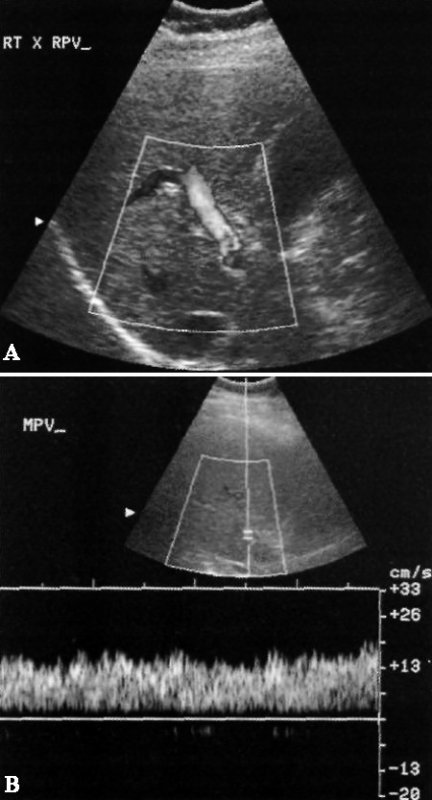

При острой или подострой портальной гипертензии из-за повышения давления увеличивается диаметр воротной вены, в результате чего снижается средний показатель скорости кровотока и формируется монотонный кровоток (без дыхательных колебаний). По мере дальнейшего повышения давления кровоток может стать двухфазным («туда-сюда») и даже обратным (фото 4).

Допплерография: Портальная гипертензия

Фото 4. Портальная гипертензия. А – цветовая допплерограмма демонстрирует венозный поток: стрелкой обозначен гепатофугальный кровоток, направленный от печени. В – спектральная допплерограмма правой воротной вены подтверждает гепатофугальный кровоток